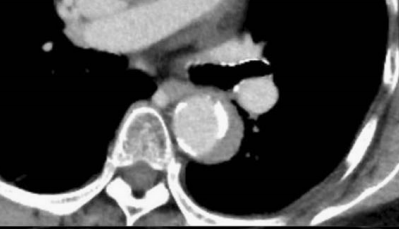

你看,我家的CT这么模糊,平扫怎么看主动脉夹层?

图18

不着急!仔细看,血管里面的“血液”居然钙化了!这叫血管钙化内移,要警惕主动脉夹层!有研究发现,血管钙化内移诊断动脉夹层的特异性高达90%。

图19

赶紧做个增强CT!主动脉裂开了!

图20